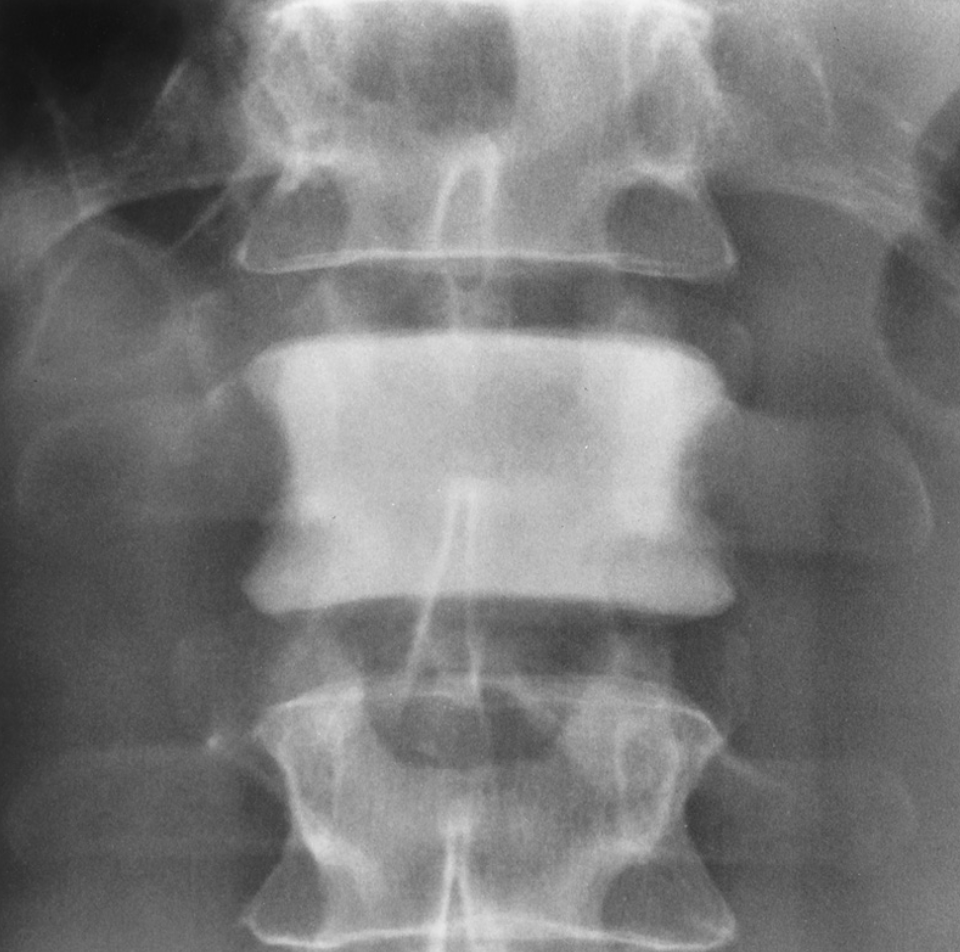

ivory vertebrae (densed vertebrae)

skeletal appearance of lymphoma